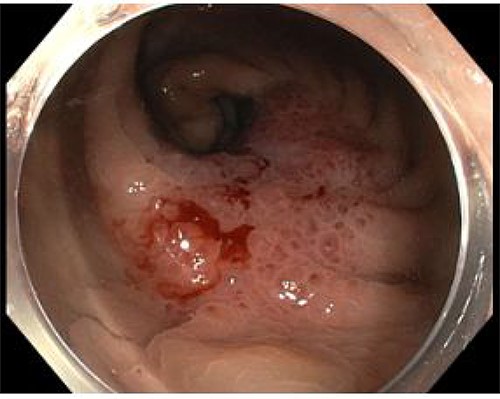

An 82-year-old man with no significant medical history presented with progressive change in bowel habit and abdominal pain for 2 months. Colonoscopy 1 year prior had only revealed diverticulosis but on rectal examination at re-presentation a firm mass was palpable within the rectum. Colonoscopy was repeated and revealed an ulcerated non-obstructing low-rectal mass 3 cm in size (Fig. 1). Biopsies reported adenomatous change with at least high-grade dysplasia and a focus suspicious for invasive adenocarcinoma.

Case A. Endoscopic image at time of initial diagnosis with rectal tumour, prior to neoadjuvant chemoradiation.